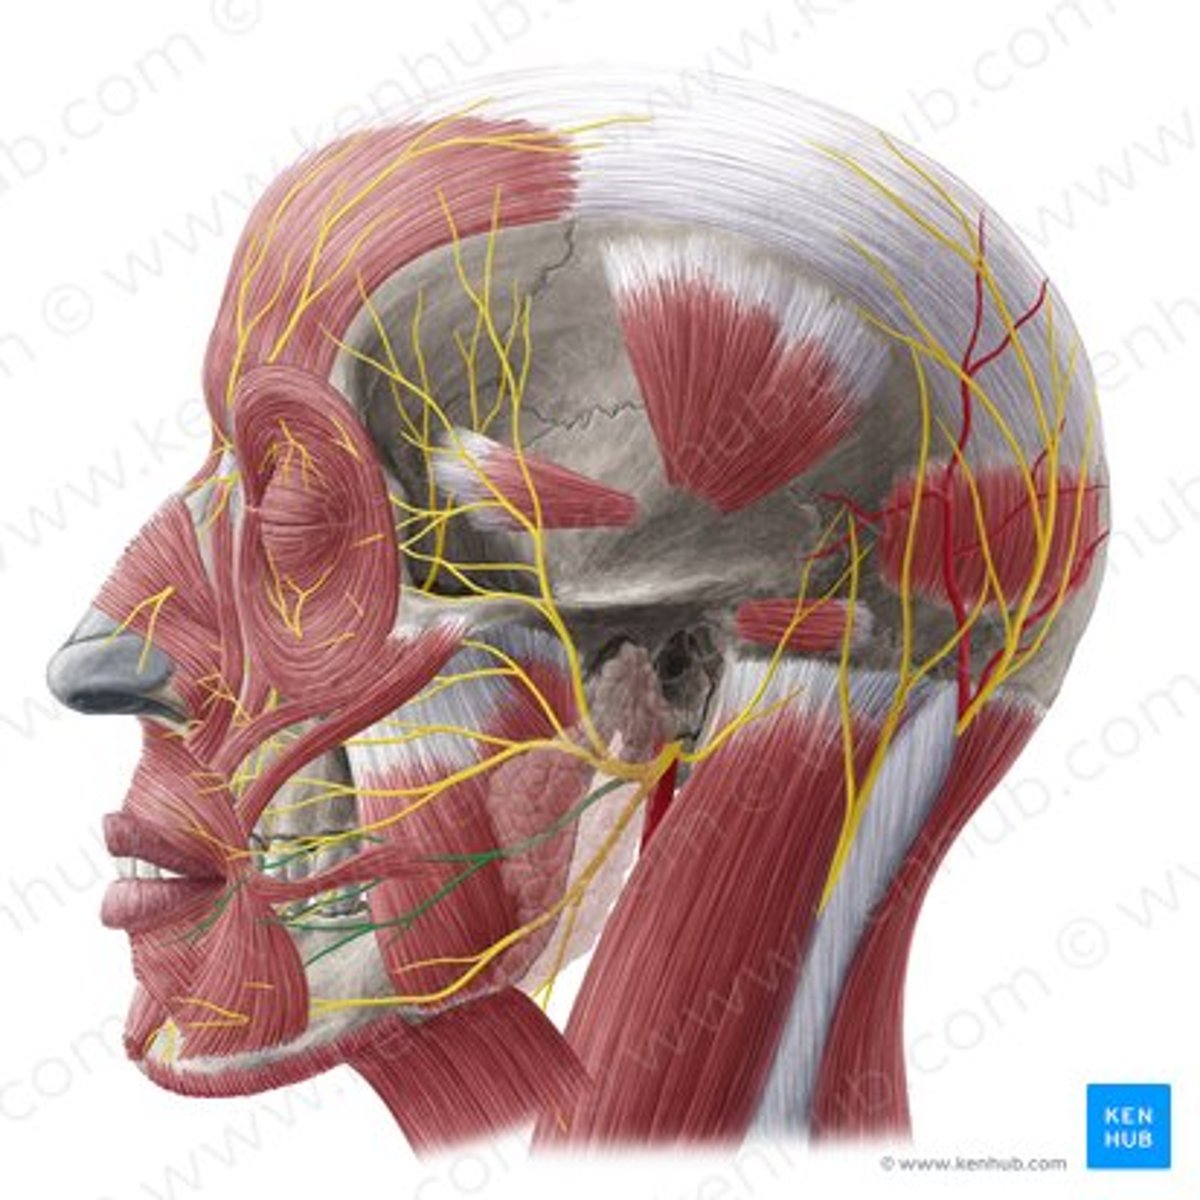

mental nerve

lingual nerve

buccal nerve